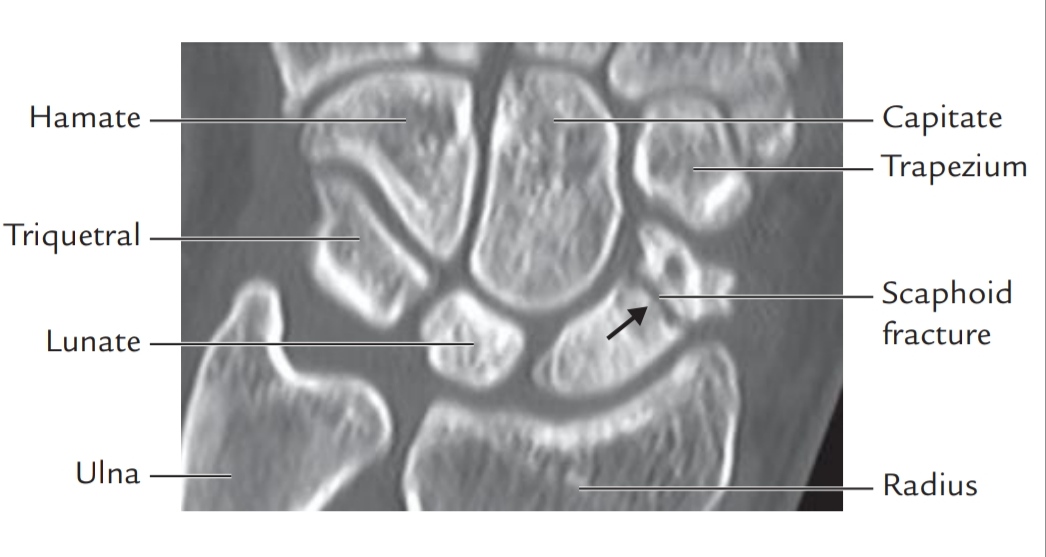

Fractures:

1.Fractures of Scaphoid is quite common. Scaphoid fractures occurs,when fallen from the height with outstretched hands.

It causes swelling and tenderness in Anatomical Snuff Box, thumb and index finger. Pain is usually felt in the Anatomical Snuff Box.